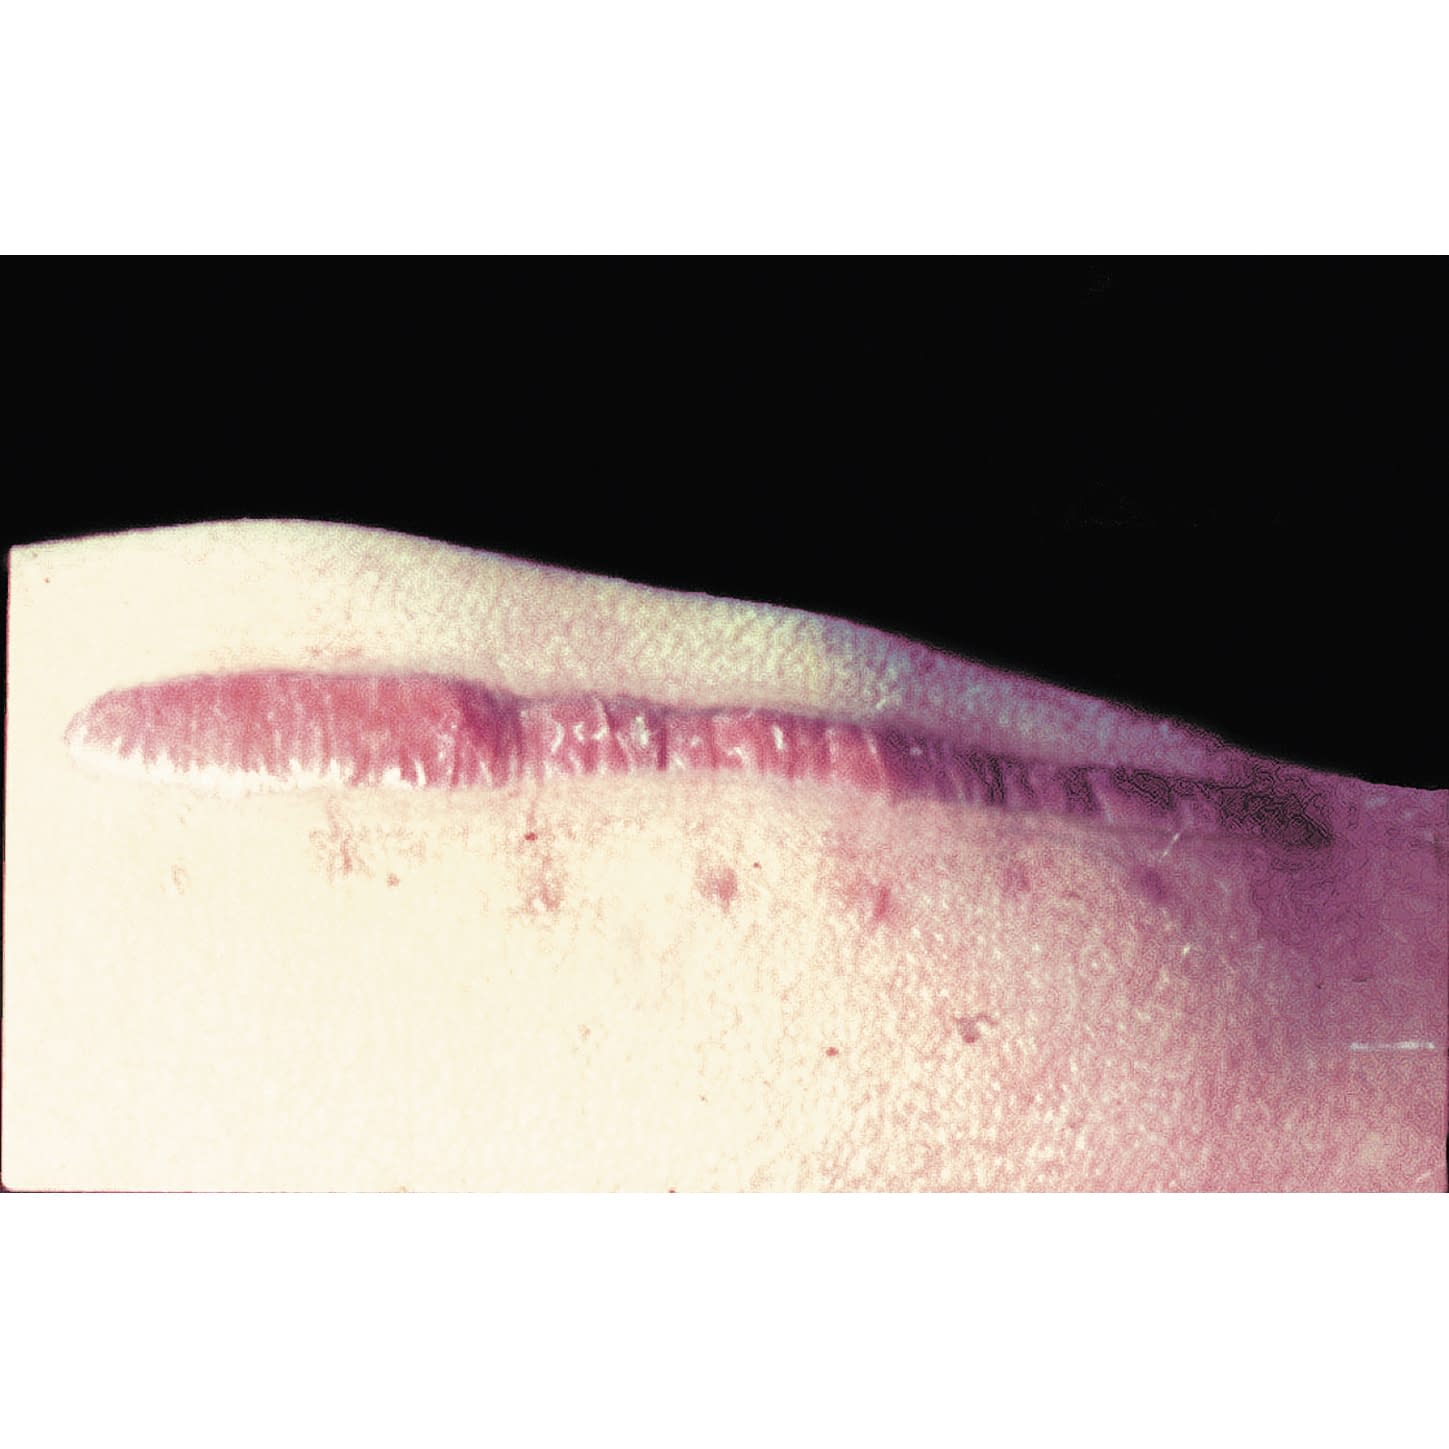

メピフォーム シリコンジェルシート 22-2055-00 メピフォーム 293100(4X30)5マイイリ|マツヨシ【松吉医科器械】医療・介護用品の総合サイト

メピフォーム シリコンジェルシート 22-2055-00 メピフォーム 293100(4X30)5マイイリ|マツヨシ【松吉医科器械】医療・介護用品の総合サイト,

メピフォーム シリコンジェルシート 22-2055-00 メピフォーム 293100(4X30)5マイイリ|マツヨシ【松吉医科器械】医療・介護用品の総合サイト,![メピフォーム 5×7.5cm(バラ売り:1枚) [ネコポス対象商品]-ハッピーハート メディカルサプライ メピフォーム 5×7.5cm(バラ売り:1枚) [ネコポス対象商品]-ハッピーハート メディカルサプライ](https://makeshop-multi-images.akamaized.net/koshiya01/shopimages/77/06/1_000000000677.png?1678209904) メピフォーム 5×7.5cm(バラ売り:1枚) [ネコポス対象商品]-ハッピーハート メディカルサプライ,

メピフォーム 5×7.5cm(バラ売り:1枚) [ネコポス対象商品]-ハッピーハート メディカルサプライ, 楽天市場】メンリッケヘルスケア メピフォーム 293400(10×18)5枚入 : ひと、モノショップ。,